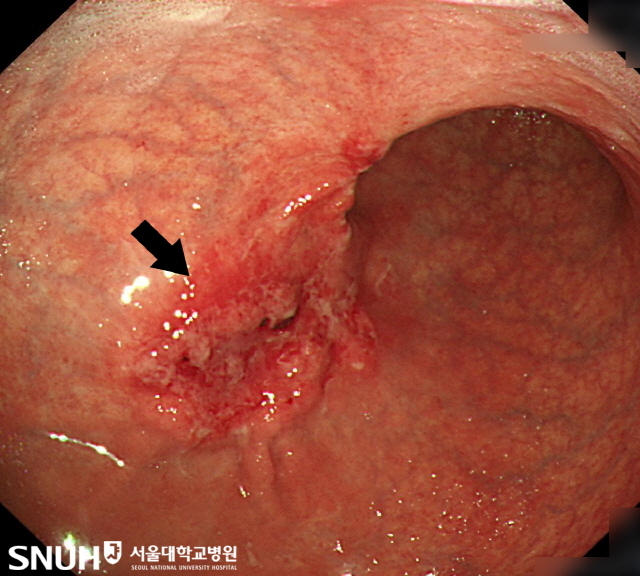

위암 환자의 내시경 영상/서울대병원 제공

또다른 이유는 조기 진단이다. 위암의 40~50%는 선종 같은 선행성 병변이 있다. 위 선종은 수개월에서 수년에 걸쳐 위암으로 진행하며, 조직학적 소견에 따라 적게는 1% 많게는 30% 정도에서 진단 당시 이미 암세포를 포함하고 있다. 위내시경이 일반화되면서 선종 단계 절제를 하는 경우가 늘었다. 위암으로 진행하기 전에 미리 조치를 하면서 위암이 조금씩 줄고 있는 것이다.

위암 초기에는 증상이 거의 없다. 증상이 있다고 하면 위암과 함께 있는 위축성 위염 때문일 가능성이 높다. 위암 때문에 증상이 나타난다면 위암이 상당히 진행된 상태일 수 있다. 대표적인 증상이 소화불량, 속쓰림이다. 암이 더 진행하면 복통, 출혈, 장폐색 등이 온다. 위 점막이 벗겨지면서 출혈이 생기고, 입으로 피를 토하고 흑색변을 보기도 한다. 장폐색까지 오면 트림에서 안 좋은 냄새가 나거나 구토를 하게 된다. 암 더 진행되면 체중감소, 황달, 천공 등이 나타난다. 그러나 진행성 위암이라고 해서 모두 증상이 나타나는 것은 아니다. 4기 위암 환자도 절반은 증상이 없다. 그래서 정기적으로 위내시경 검사를 받아야 한다.